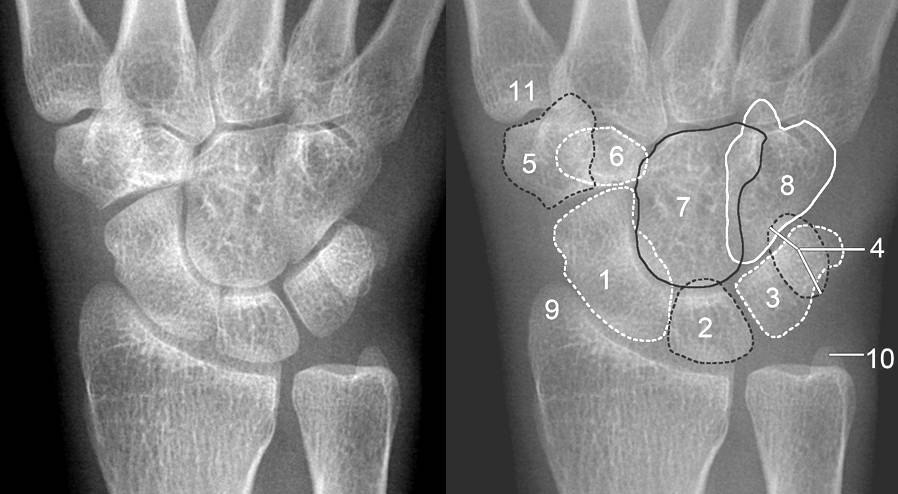

手首にある 8 つの小さな骨 (手根骨) のうち、三角筋は最も損傷を受けやすいものの 1 つです。手首の外側にある三角の骨です。三角筋を含むすべての手根骨は、前腕と手の間に 2 列に並んでいます。

次に、手と手首のX 線検査を依頼される可能性があります。画像では、三角筋骨折は、小さな骨片が三角筋の後ろから剥がれたように見えます。